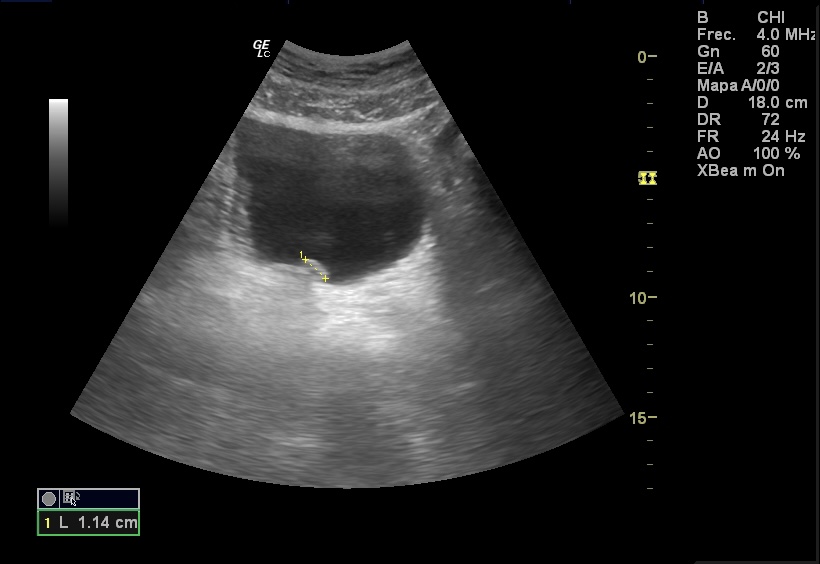

Hallazgos ecográficos

Ecografía abdominal y renal sin hallazgos. En la vejiga se aprecia una lesión polipoidea hiperecogénica irregular de bordes lobulados, de 1,23 cm de diámetro dependiente de la pared vesical en la región del trígono vesical.